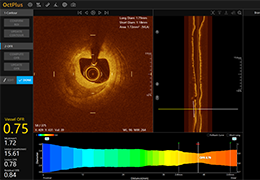

ANYTHINK 经导管主动脉瓣膜置换术分析系统